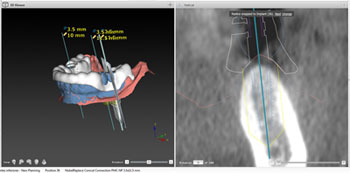

El centro dispone de un equipo de profesionales especializados en las diferentes áreas de la odontología para ofrecerte las soluciones más avanzadas, utilizando tecnología de ultima generación para el diagnostico, así como materiales de máxima calidad en todos nuestros tratamientos. De igual manera trabajamos con diferentes laboratorios de prótesis dental especializados en diferentes áreas para la confección de los trabajos protésicos.

Disponemos de 6 gabinetes de tratamiento totalmente equipados con aparatologia de ultima generación, incluyendo radiología digital intraoral (radiovisiografía), asi como cámaras intraorales en todos ellos para facilitar el diagnostico y la comunicación con el paciente.